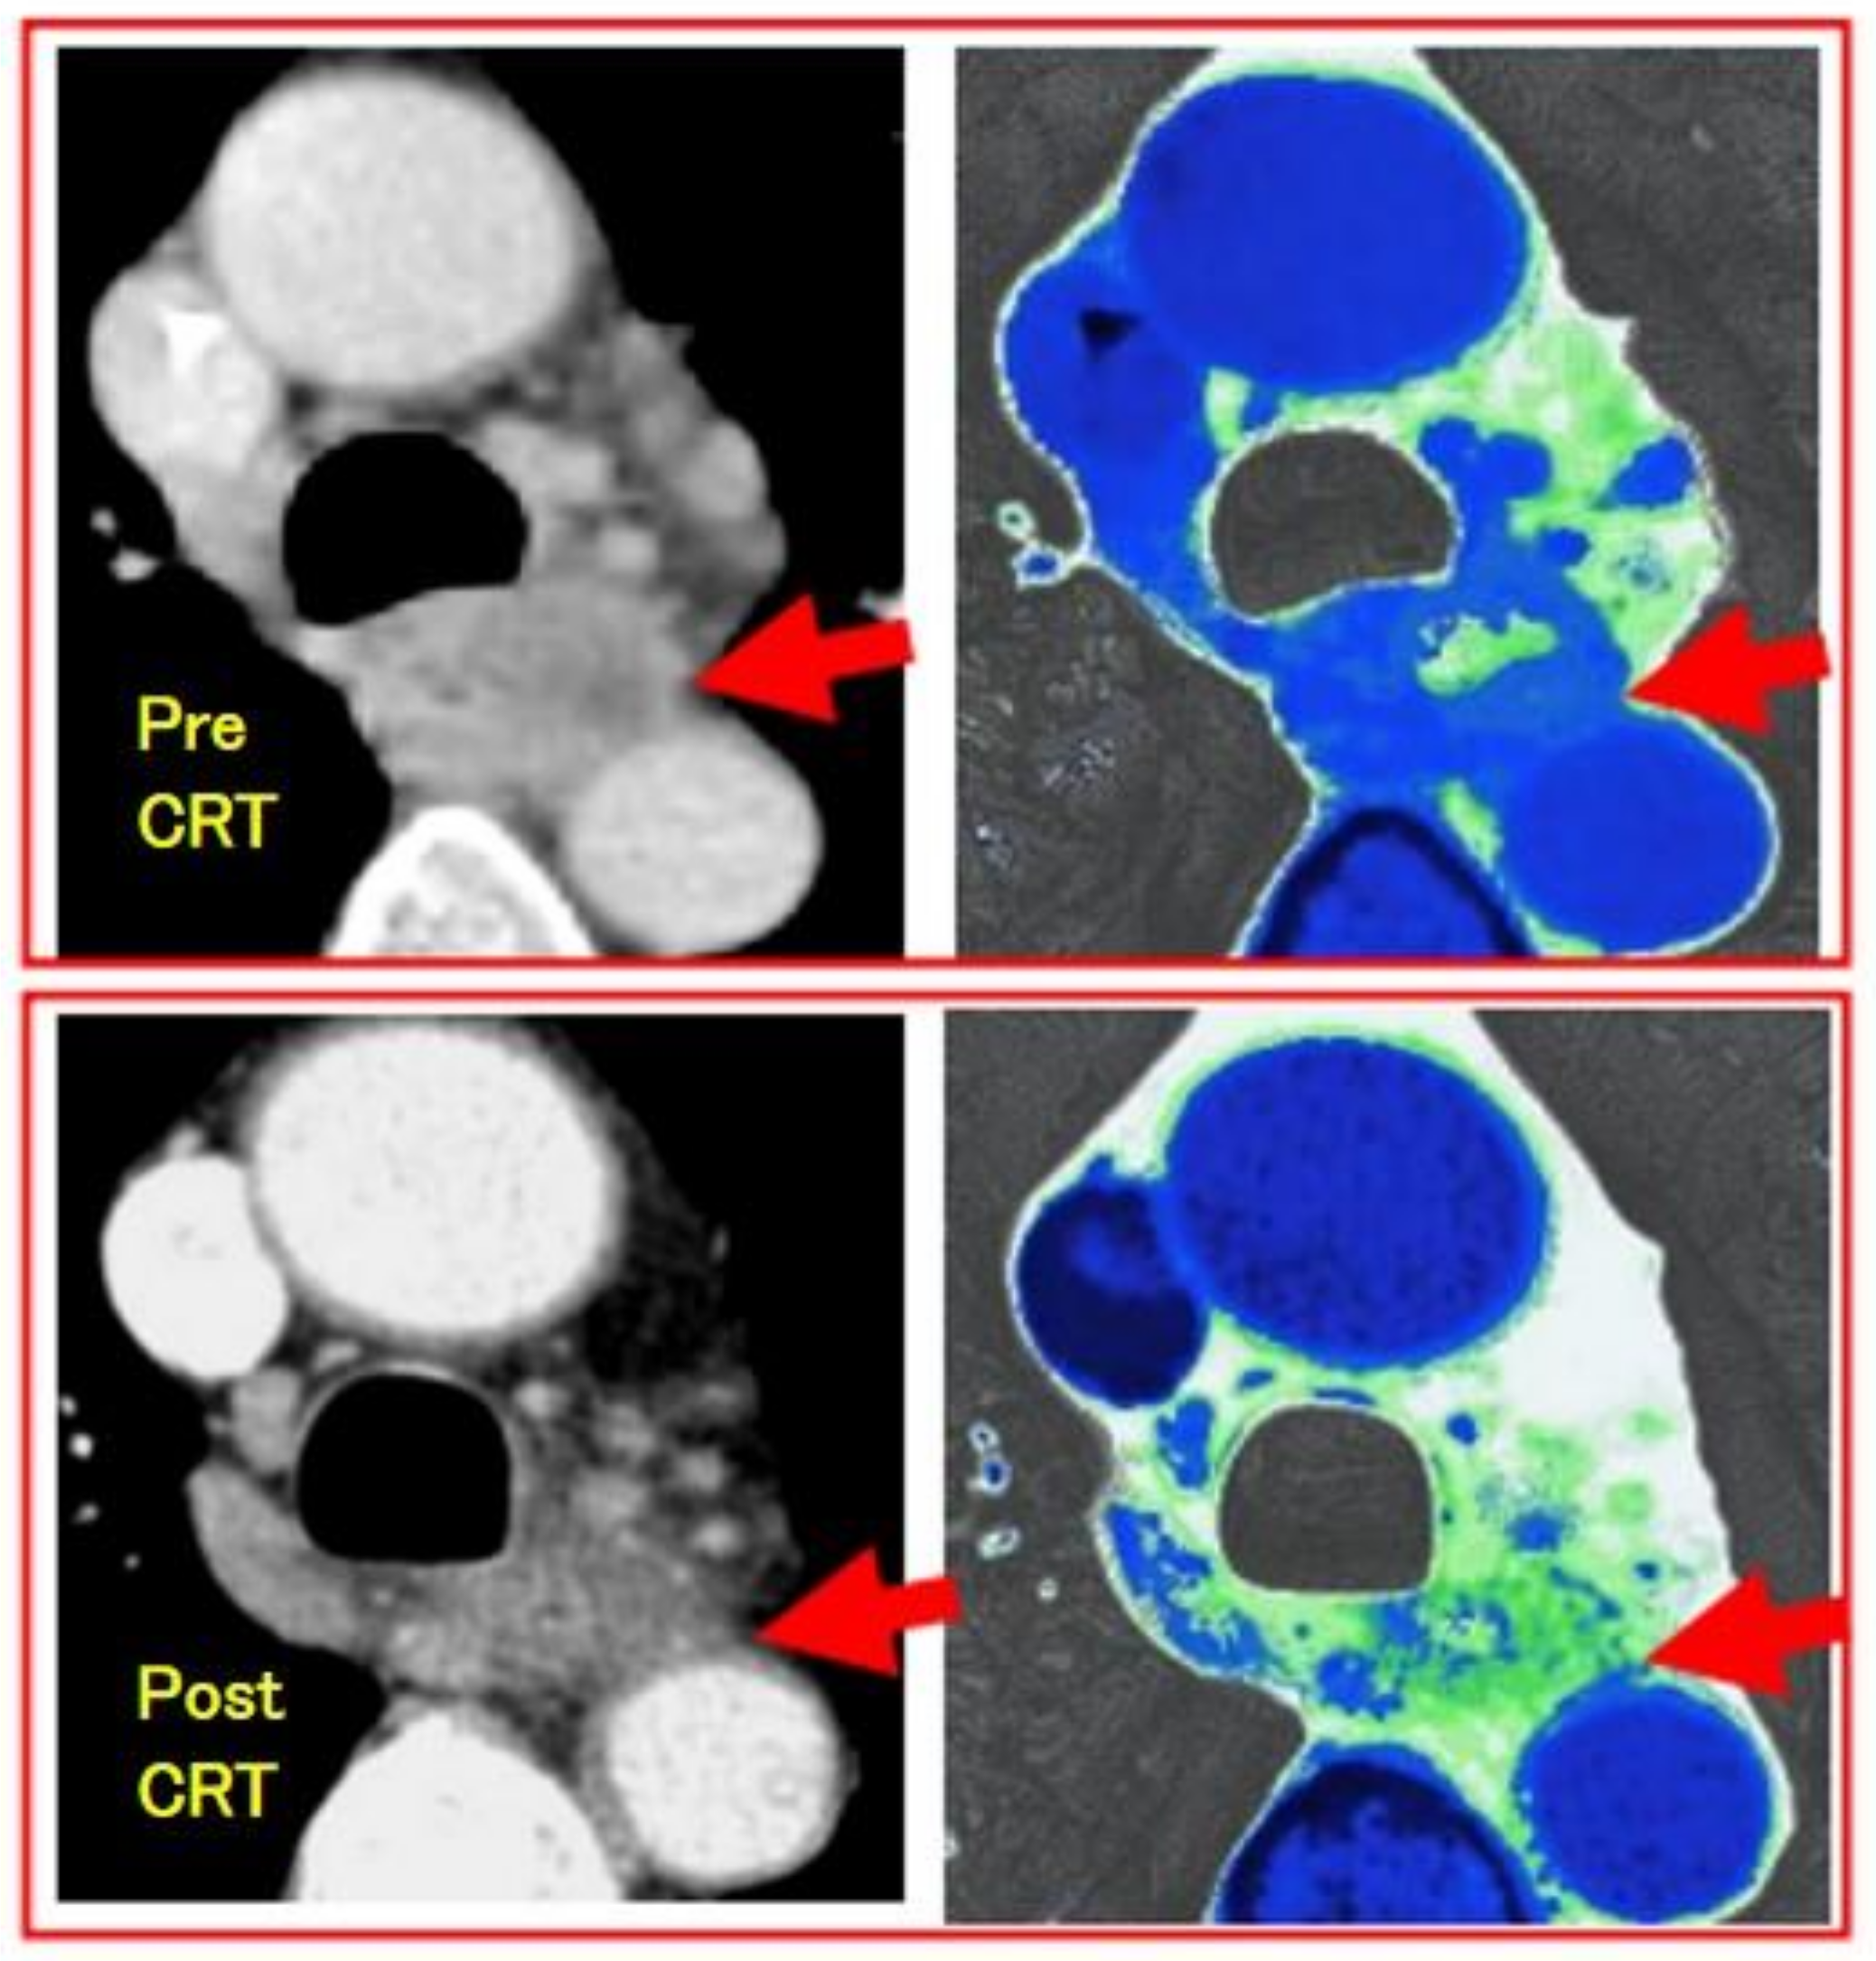

- Djuric-Stefanovic, A.; Micev, M.; Stojanovic-Rundic, S.; Pesko, P.; Saranovic, D. Absolute CT perfusion parameter values after the neoadjuvant chemoradiotherapy of the squamous cell esophageal carcinoma correlate with the histopathologic tumor regression grade. Eur. J. Radiol. 2015, 84, 2477–2484. [Google Scholar] [CrossRef] [PubMed]

- Imanishi, S.; Shuto, K.; Aoyagi, T.; Kono, T.; Saito, H.; Matsubara, H. Diffusion-weighted Magnetic Resonance Imaging for Predicting and Detecting the Early Response to Chemoradiotherapy of Advanced Esophageal Squamous Cell Carcinoma. Dig. Surg. 2013, 30, 240–248. [Google Scholar] [CrossRef] [PubMed]